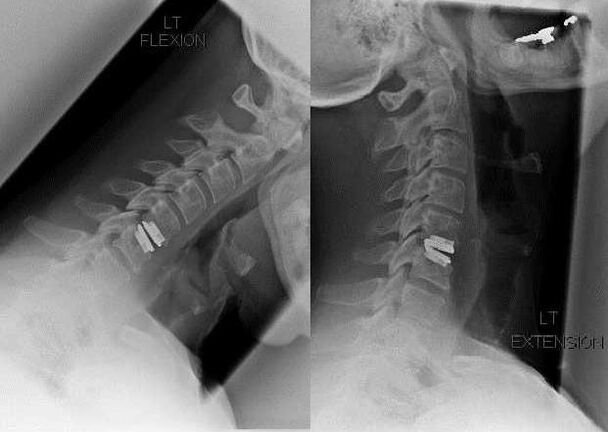

With radiographic stage 2-3 osteochondrosis, the patient complains of sharp, stabbing pain that occurs when tilting or turning the head.In such cases, they are prescribed non-steroidal anti-inflammatory drugs.For severe pain, intramuscular injections of solutions are practiced - diclofenac, meloxicam, lornoxicam, ketorolac.These drugs are not only analgesic, but also anti-inflammatory and anti-edematous.This is especially true when the soft tissue of the neck is injured by a displaced disc or osteophyte.